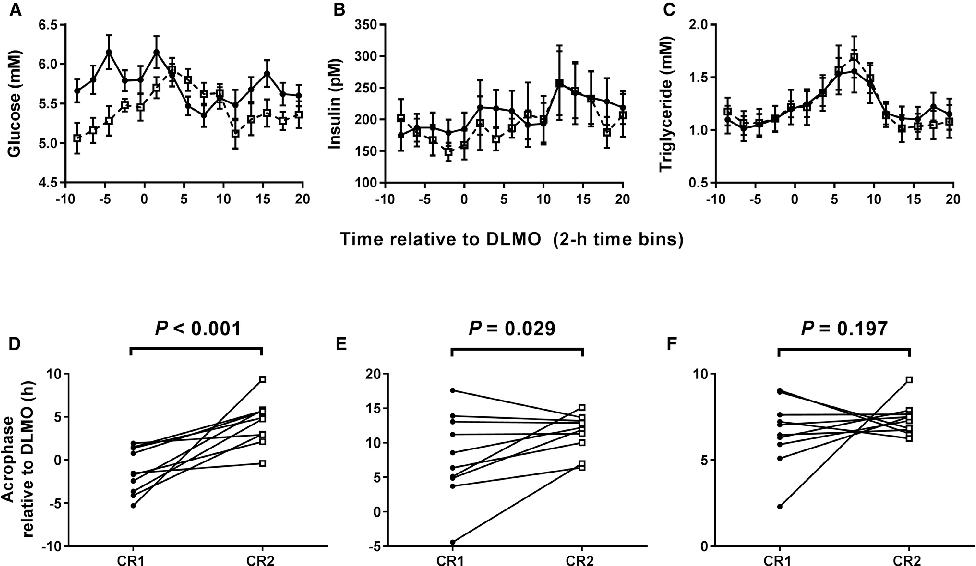

Hormonal response profiles to standardized meals are compared between normal and delayed meal timing conditions, revealing shifts in metabolic hormone rhythms.

Meal Timing Regulates the Human Circadian System.

Clock gene expression patterns in adipose tissue are compared between the two meal timing conditions, revealing tissue-specific circadian phase shifts.

Meal Timing Regulates the Human Circadian System.